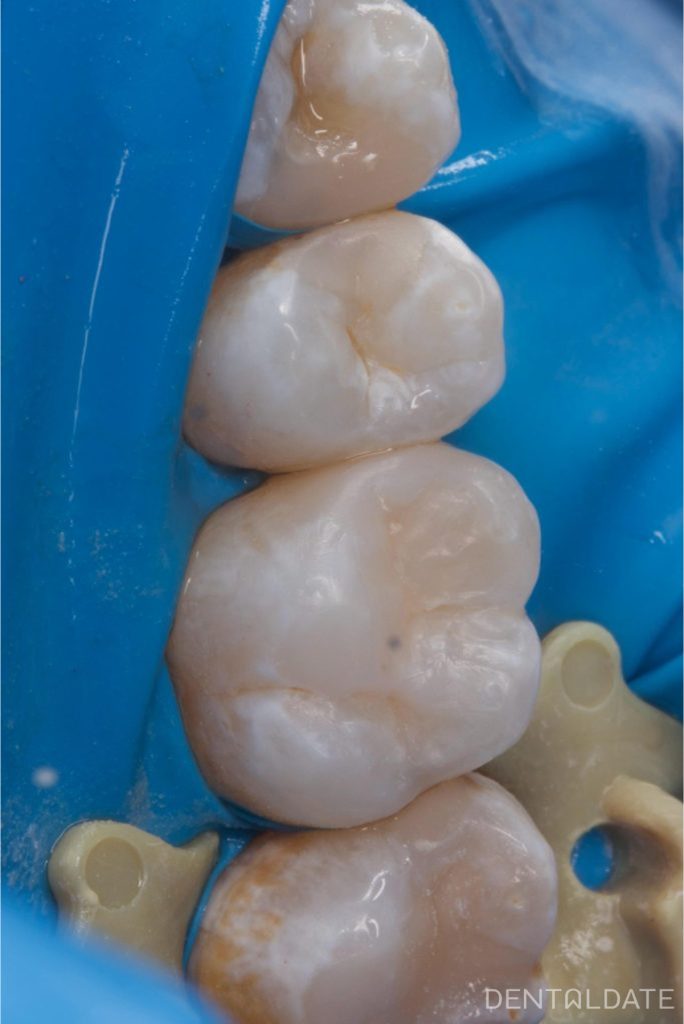

The teeth are fully anatomically restored, with tight contact maintained to avoid food ingestion.